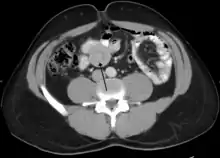

Small intestinal invagination on computed tomography

An ultrasound shows a target sign—characteristic for intussusception

An intussusception is often suspected based on history and physical exam, including observation of Dance's sign. A digital rectal examination is particularly helpful in children, as part of the intussusceptum may be felt by the finger. A definite diagnosis often requires confirmation by diagnostic imaging modalities. Ultrasound is the imaging modality of choice for diagnosis and exclusion of intussusception, due to its high accuracy and lack of radiation. The appearance of target sign (also called "doughnut sign" on a sonograph, usually around 3 cm in diameter, confirms the diagnosis. The image seen on transverse sonography or computed tomography is that of a doughnut shape, created by the hyperechoic central core of bowel and mesentery surrounded by the hypoechoic outer edematous bowel.[11] In longitudinal imaging, intussusception resembles a sandwich.[11] It is also called "pseudokidney" sign because hyperechoic tubular centre is covered by a hypoechoic rim producing a kidney-like appearance.[12]